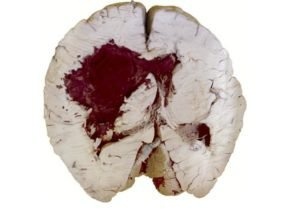

Травмы головы, вызванные внешним воздействием, например, падением или ударом, приводят к неравномерному диаметру зрачка. Церебральные кровоизлияния происходят внутри черепа и не вызывают внешних симптомов. Попадание большого количества крови в ткани мозга приводит к сдавливанию структур.

Если нервы (нервы мозга), отвечающие за расширение и сужение зрачков, сдавливаются с одной стороны, а кровотечение на противоположной стороне не вызывает сдавливания, зрачки становятся разного диаметра.

Опасными для жизни симптомами тяжелого кровоизлияния в мозг являются спутанность и потеря сознания, а также конвульсии.

В случае травм головы, которые вызывают различные размеры зрачков, необходимо как можно скорее доставить пациента в больницу. Сначала проводится компьютерная томография головы. Если обнаружено кровоизлияние в мозг, его лечат хирургическим путем, в зависимости от размера кровоизлияния.